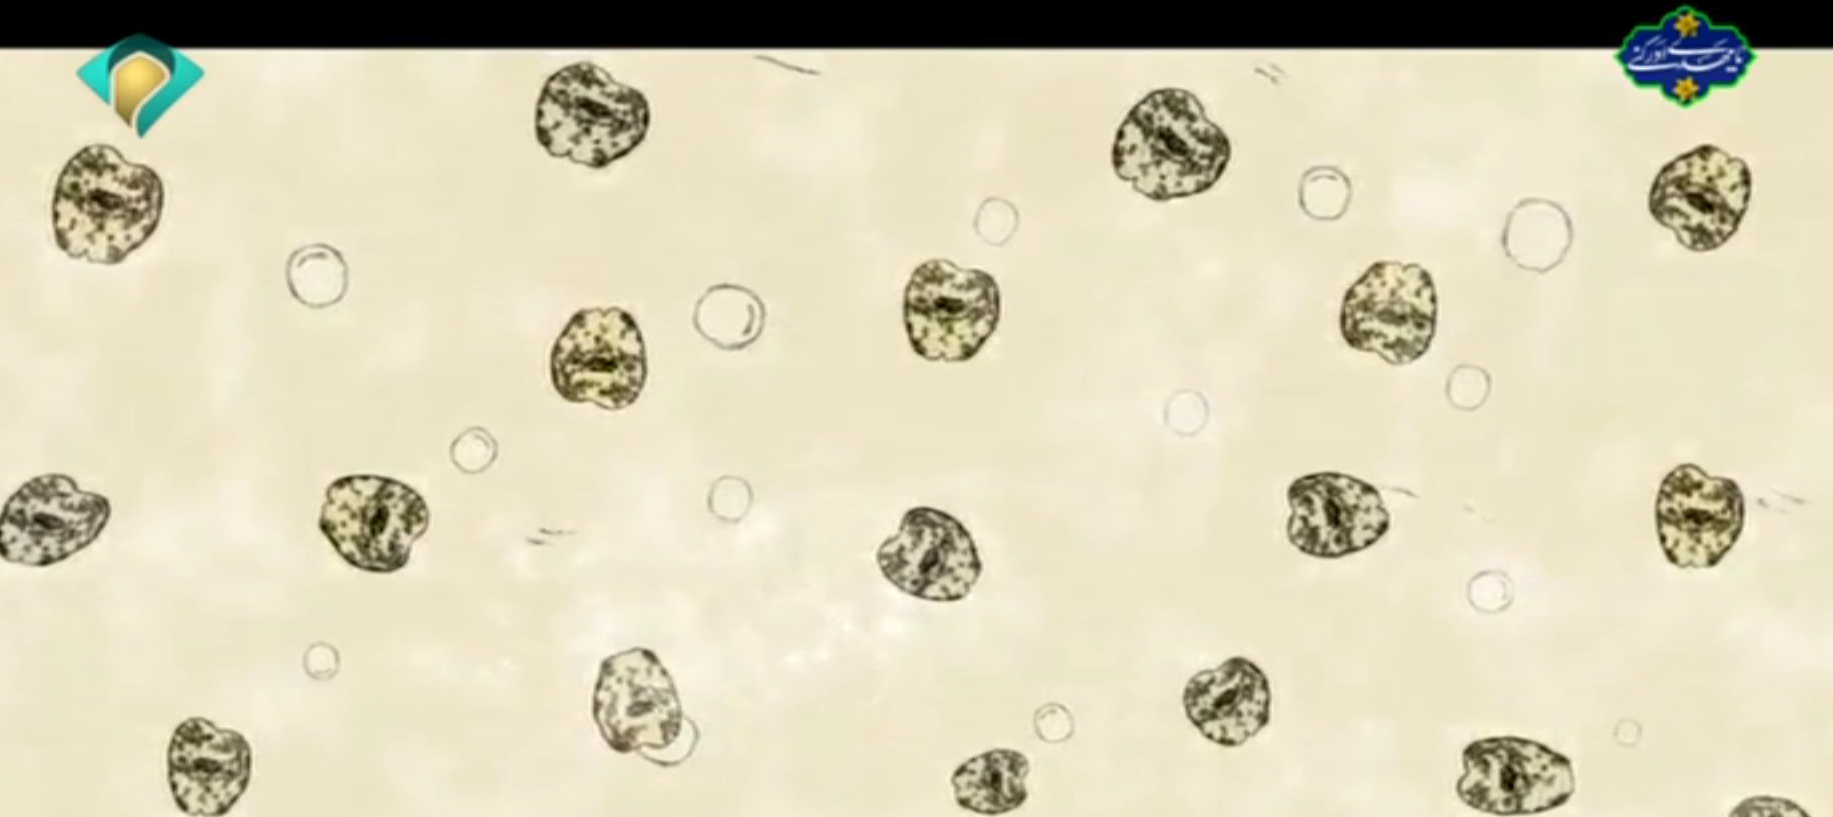

آرشیو انعکاس روزانه دانشگاه در رسانه ها پزشک شما 03 اسفند 1402 بازدید: 90 امتیاز: ( 0 Rating ) برنامه پزشک شما با موضوع بیماری انگلی ریه و کبد با حضور دکتر علی صدر زاده فوق تخصص جراحی قفسه سینه پنجشنبه 3 اسفندماه 1402/ تلویزیون خراسان رضوی امتیاز کاربران لطفا رای دهید رای 1 رای 2 رای 3 رای 4 رای 5 لینک تلوبیون موضوع برنامه : برنامه پزشک شما با موضوع بیماری انگلی ریه و کبد با حضور دکتر علی صدر زاده فوق تخصص جراحی قفسه سینه پنجشنبه 3 اسفندماه 1402/ تلویزیون خراسان رضوی ارتباط زنده : دکتر جعفر نژاد معاون فنی مرکز بهداشت استان خراسان رضوی گزارش: گزارش دستاورد های دانشگاه علوم پزشکی گناباد موشن گرافی : انگل های کبدی موشن گرافی : عفونت های روده ای کاری از : روابط عمومی دانشگاه علوم پزشکی مشهد دکتر جعفر نژاد معاون فنی مرکز بهداشت استان خراسان رضوی انگل های کبدی عفونت های روده ای گزارش دستاورد های دانشگاه علوم پزشکی گناباد قبلی بعدی